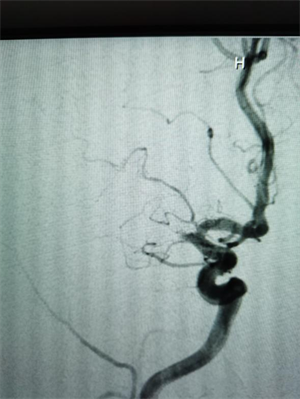

凌晨四点的“大脑保卫战”

元宵节凌晨4点,60岁的胡先生因左侧肢体无力、言语不清,被紧急转送至我院。经检查,胡先生右侧脑梗死,且仍有大片缺血低灌注区域,右侧大脑中动脉完全闭塞,情况十分危急。神经内科介入团队迅速启动卒中绿色通道,立即为其行大脑中动脉急诊再通手术。术中,医生通过球囊扩张并置入血管支架,成功实现血管再通。当晚,胡先生左侧上下肢无力症状明显改善,肢体力量恢复,言语也变得清晰。

△图一:手术前右侧大脑中动脉闭塞

△图二:手术后闭塞的大脑中动脉已再通